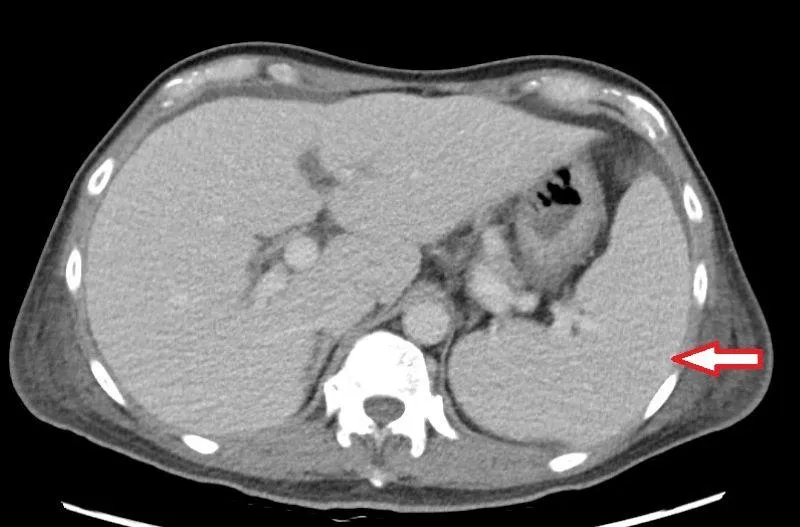

反覆高燒找不到病因!竟是「三尖瓣重度逆流」害脾臟腫大

脾臟腫大

血球減少